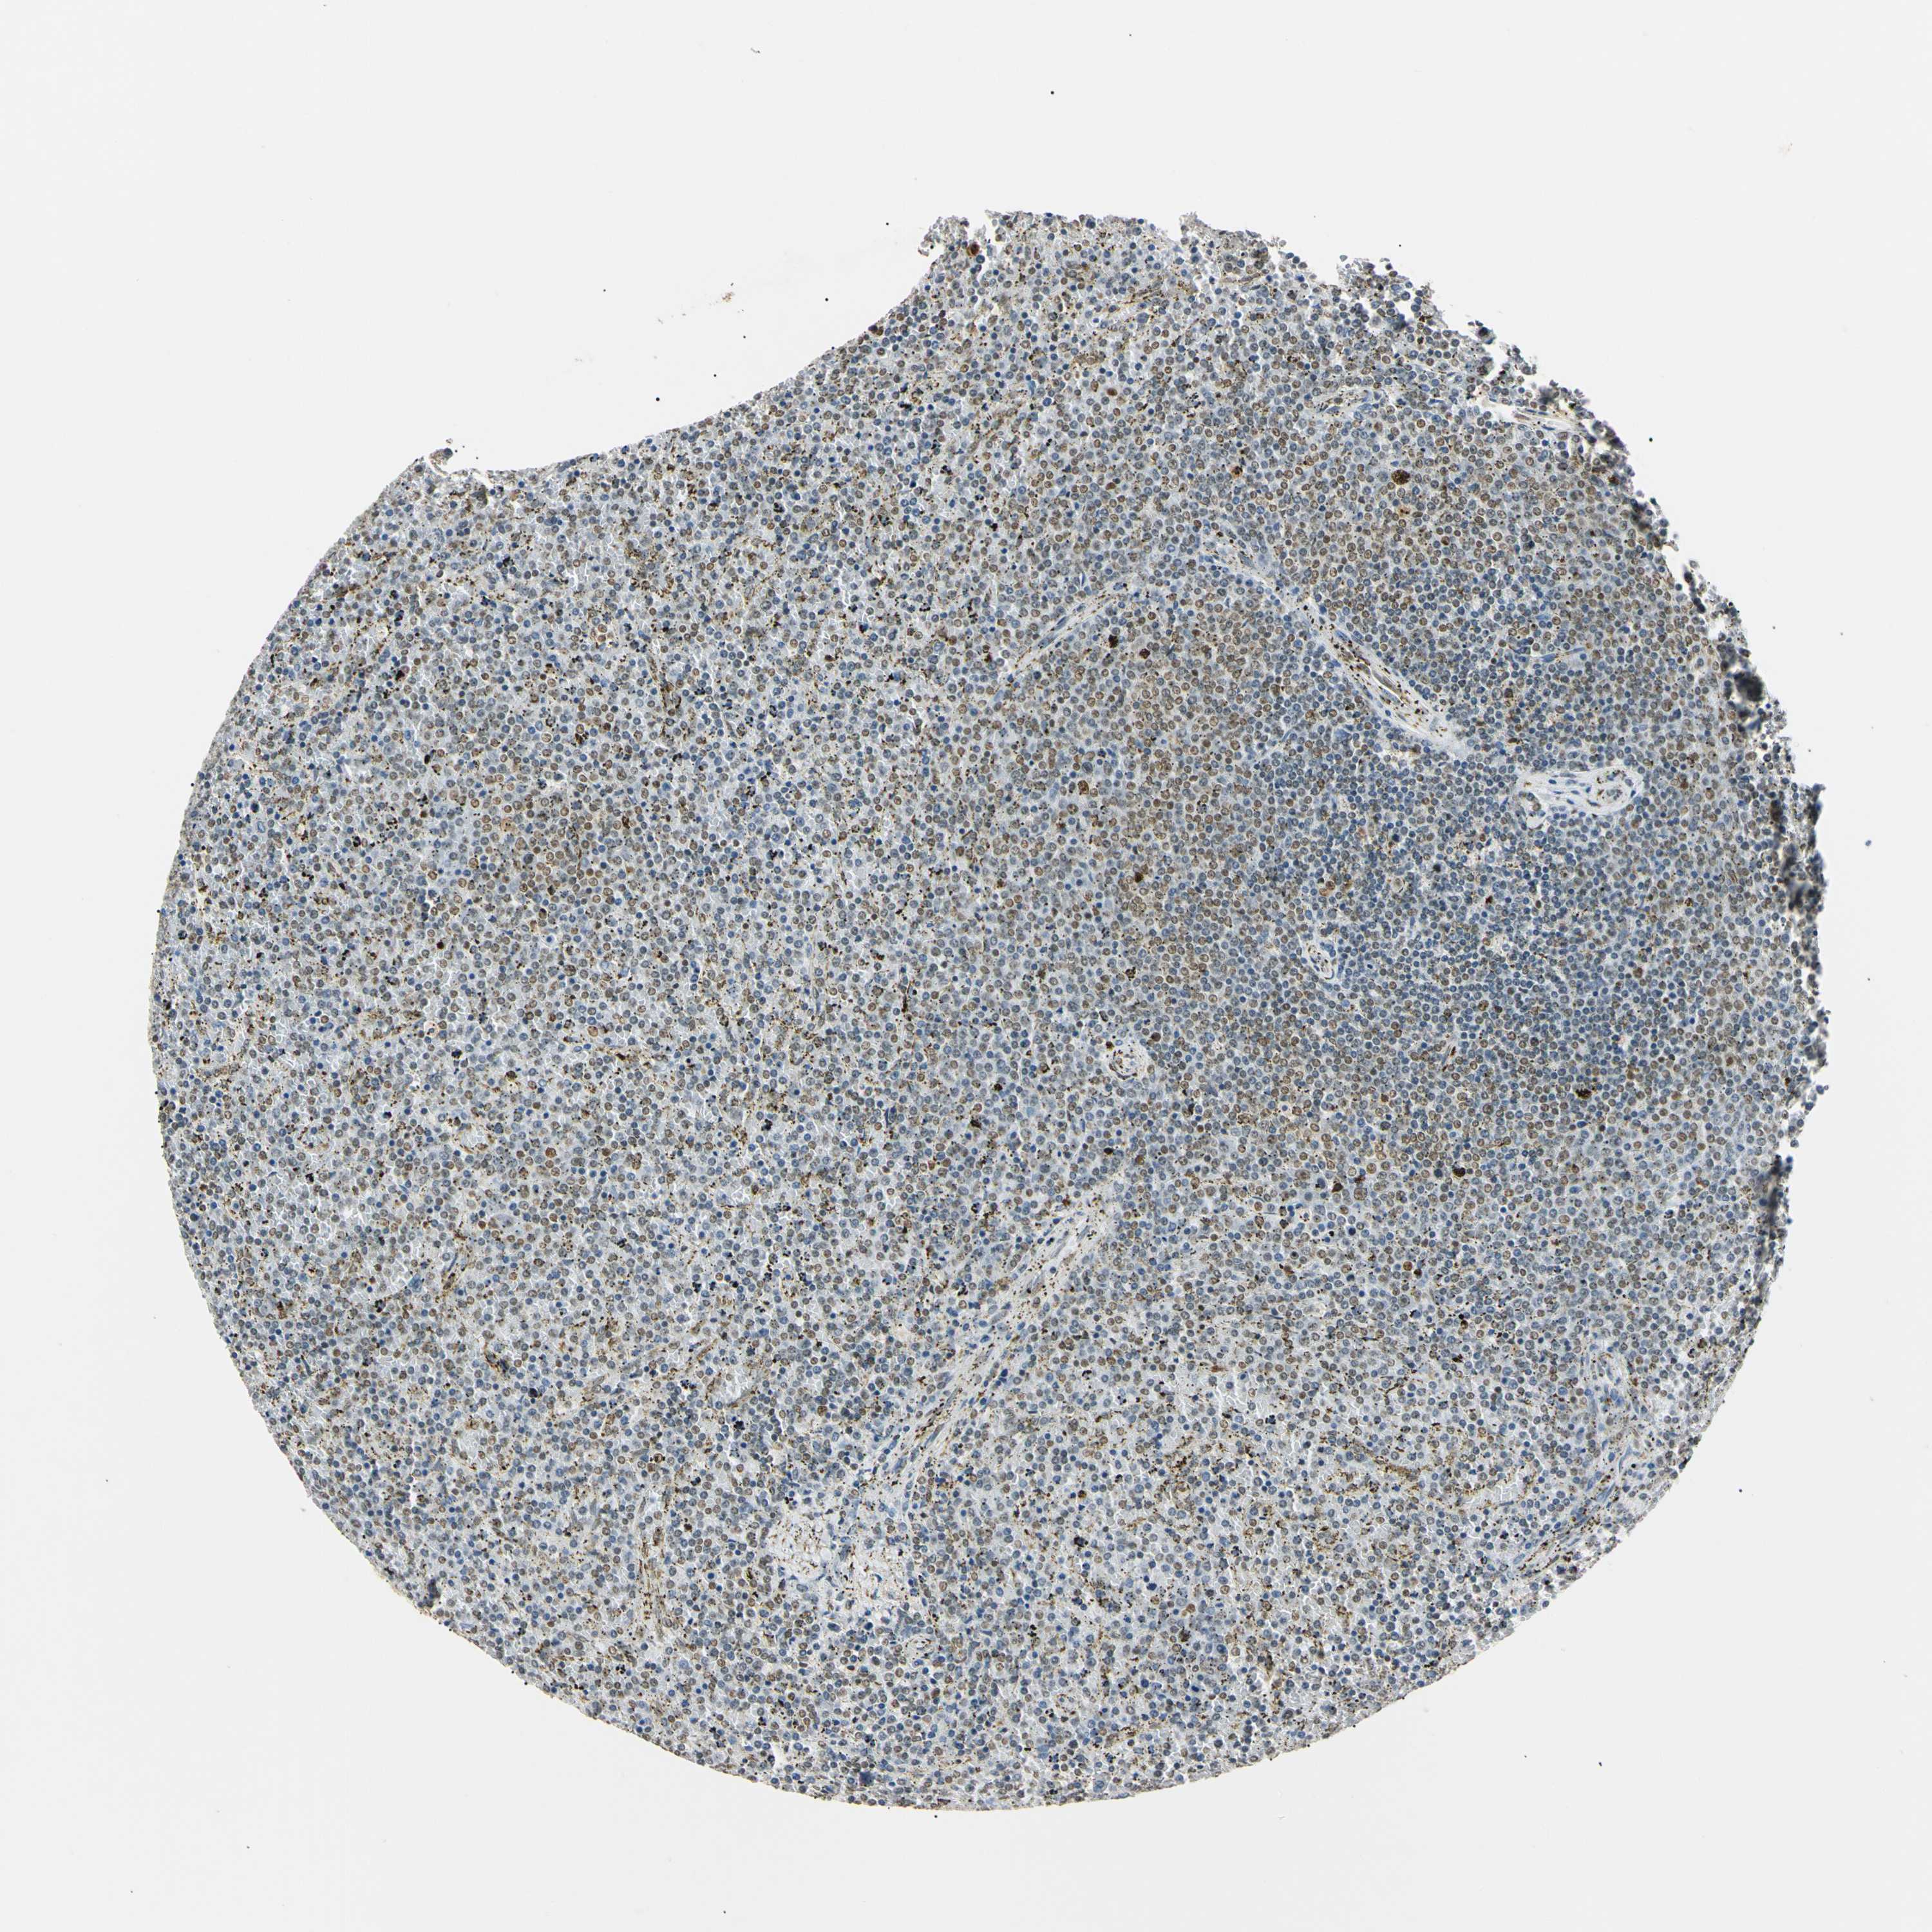

LYMPHOMA - Protein expressioni

A mouse-over function shows sample information and annotation data. Click on an image to view it in a full screen mode. Samples can be filtered based on level of antibody staining by selecting one or several of the following categories: high, medium, low and not detected. The assay and annotation is described here.

Each image is clickable and will lead to virtual microscopy that enables deeper exploration of all samples and also displays staining intensity scores, fraction scores and subcellular localization as well as patient and tissue information for each sample.

Antibody HPA008751

Staining

High

Medium

Low

Not detected

Intensity

Strong

Moderate

Weak

Negative

Quantity

>75%

75%-25%

<25%

None

Location

Nuclear

Cytoplasmic/membranous

Cytoplasmic/membranous,nuclear

Hodgkin's disease, NOS

Malignant lymphoma, non-Hodgkin's type, Low grade

Malignant lymphoma, non-Hodgkin's type, High grade